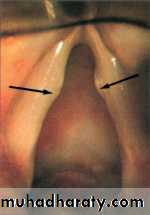

Intubation Granuloma

AetiologyIt results from injury to vocal process of

arytenoids due to rough intubation, use of large tube.

Pathology

Mucosal ulceration is

followed by granuloma

formation over the exposed

cartilage.

Clinical picture

Patients are referred few days or weeks after an operation with hoarseness of voice. Stridor is rare.On Examination:

Endoscopy reveals a fleshy granuloma arising from the vocal process of arytenoids.

Treatment

Voice rest and endoscopic removal preferably with LASER.